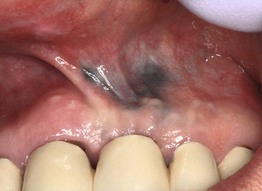

Fig. 59.15 Crohn's disease. Linear ulceration of the mandibular vestibule is the classic oral manifestation of this disease. Courtesy, Carl M. Allen, MD, and Charles Camisa, MD.

Fig. 59.16 Wegener's granulomatosis – strawberry gums. The affected areas of the gingiva are red-purple, micropapular, and friable, with a resemblance to ripe strawberries. Courtesy, Carl M. Allen, MD, and Charles Camisa, MD.